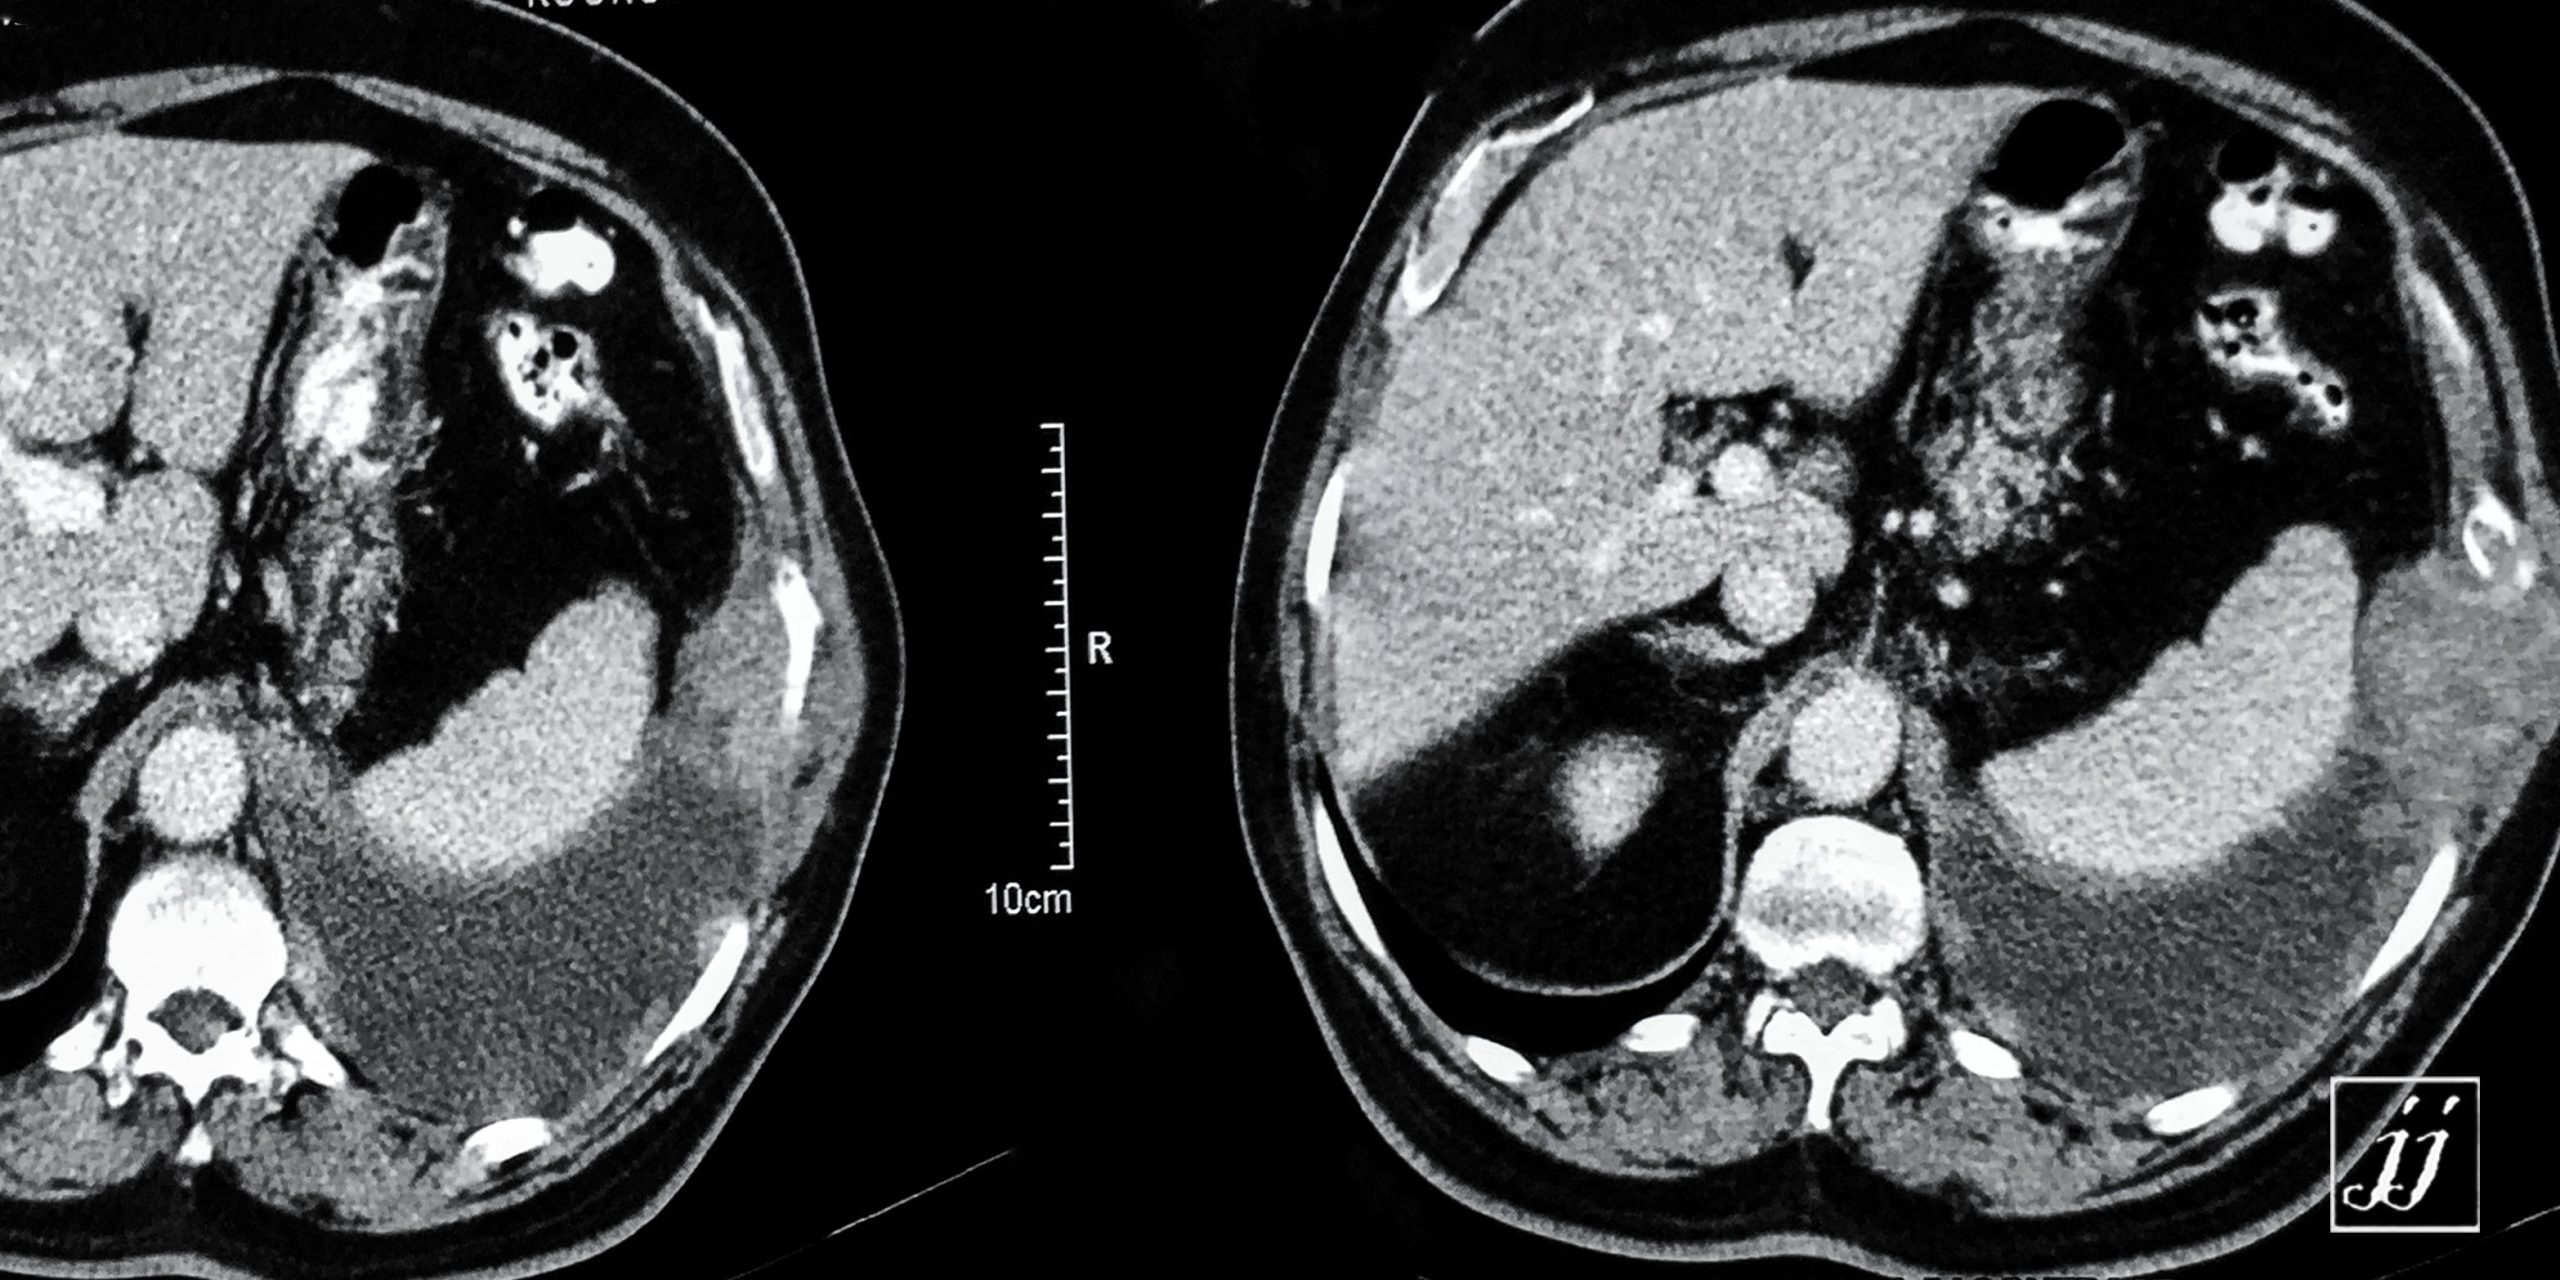

Abdomen- left side plural effusion (7)